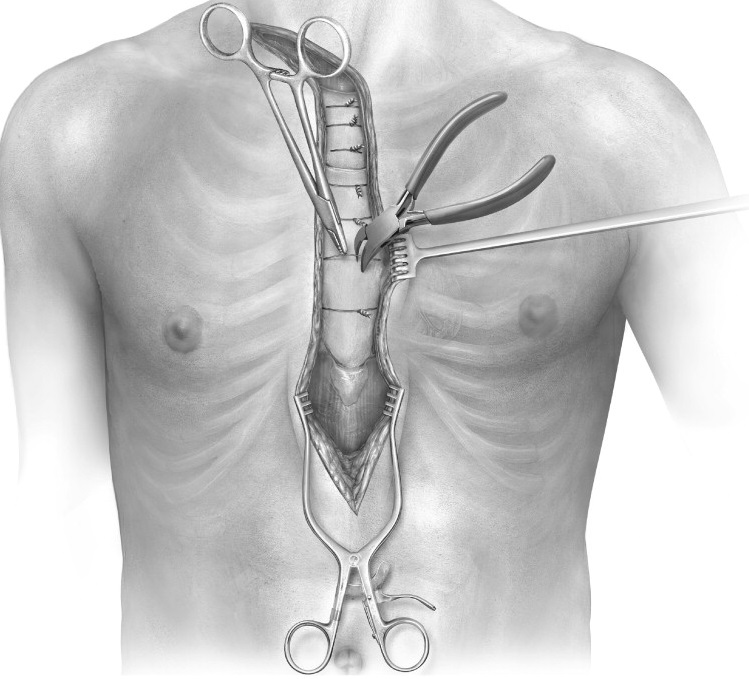

Overview

Package includes:

Days in hospital : 7 to 8 Days (For patient and one attendant)

Days in hotel : 12 Days (For patient and one attendant)

Room type in hospital : Shared

Room type in hotel : Private

Hotel category: Standard

Value added benefits of the CABG:

Ø Doctor consultation charges

Ø Lab tests and diagnostic charges

Ø Room charges inside hospital during the procedure

Ø Surgeon Fee

Ø Nursing charges

Ø Hospital surgery suite charges

Ø Anesthesia charges

Ø Routine medicines and routine consumables (bandages, dressings etc.)

Ø Food and Beverages inside hospital stay for patient and one attendant.

Extra benefits:

ü Interpreter

ü Visa assistance

Ø Site tourism of the city

Ø Follow up with the doctor

Ø Airport pick up and drop

Ø Free online consultation with the doctor

Ø Priority appointments with the doctor

Ø Room upgrade from sharing to private